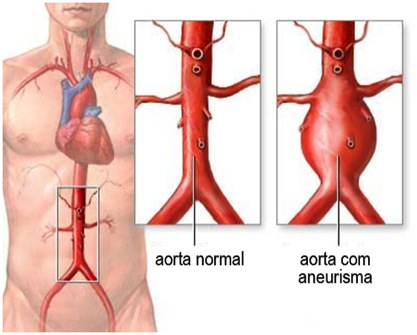

Aneurisma de aorta

Aneurisma significa uma dilatação permanente de uma artéria. Pode ocorrer em todas as artérias do corpo humano mas as mais frequentes são da aorta (principal artéria do corpo que começa no coração e termina na altura do umbigo), poplítea (artéria que fica atrás do joelho), ilíacas (artérias que se localizam na pelve) e cerebrais.

A grande importância dos aneurismas é que elas podem romper, muitas vezes resultando em quadros gravíssimos. Alem do risco de rotura, podem trombosar (“entupir” a circulação) ou jogar pedaços de coágulos para a circulação distal. O grande problema dos aneurismas é que, na maioria dos casos, eles são assintomáticos, ou seja, o indivíduo que o possue não sente nada. Às vezes, a primeira manifestação clínica pode ser decorrente de alguma complicação do aneurisma. Mas, calma… Não é necessários sair correndo para fazer um check up completos das suas artérias. Primeiro, porque os aneurismas não são tão comuns assim. Apenas uma pequena parcela da população vai desenvolver algum durante sua vida. Além disso, nem todos os aneurismas rompem.